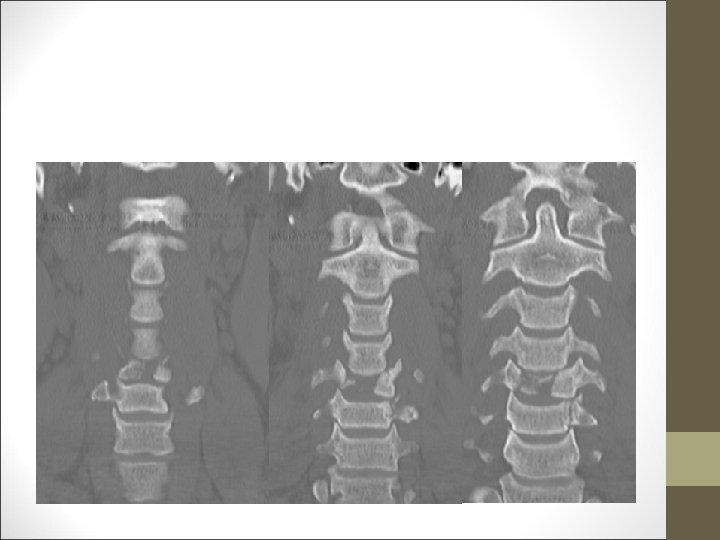

FACULTAD DE MEDICINA DEPARTAMENTO DE CIRUGÍA NEUROCIRUGÍA ¿Qué harías? TAC Cervical

TC Desplazamientos de fragmentos óseos ¿Algo mas? FACULTAD DE MEDICINA DEPARTAMENTO DE CIRUGÍA NEUROCIRUGÍA RM Desplazamientos discales y lesiones ligamentosa